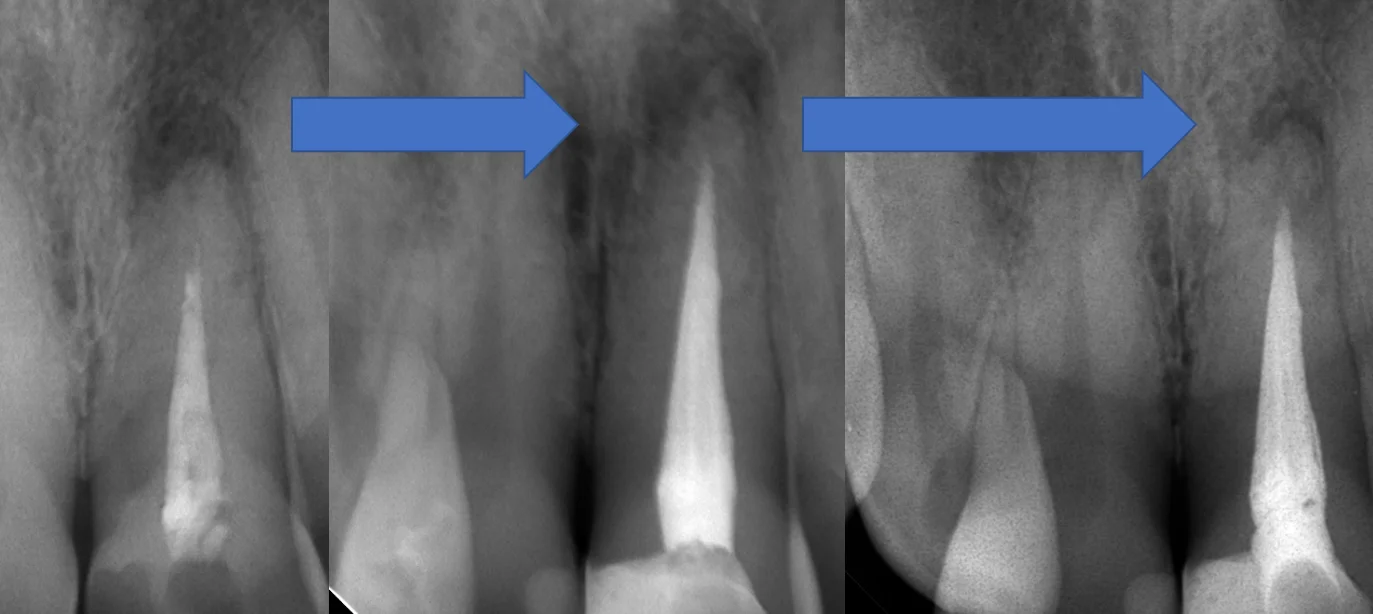

治療スタート時→根管充填時→根管充填から1年経過後のレントゲンがこちらです。

分かりやすくするために歯のサイズを大体揃えてみました。

根の先の膿が大分小さくなってきているのが分かるかと思います!

神経の治療後、この方はかなり歯が残っている状態だったので、そのまま保険の白い詰め物で終了しています。